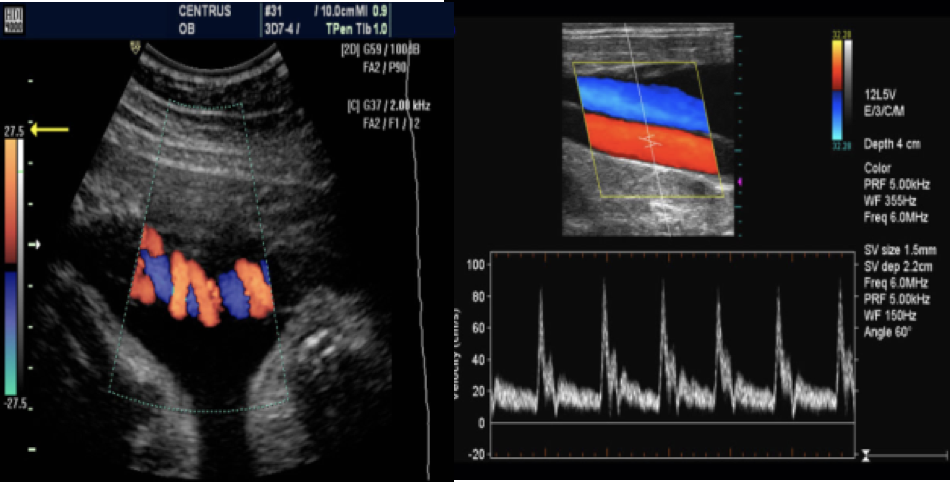

Doppler ultrasound

Doppler studies are used to detect #Z venous thrombosis, arterial stenosis and occlusion.

Ā Doppler or duplex mode used to visualize motion within structures, e.g., the velocity and direction of blood flow.

In obstetrics, Doppler ultrasound is used particularly to Z determine fetal blood flow through the umbilical artery

With Doppler echocardiography it is possible to demonstrate Z Regurgitation through incompetent valves.